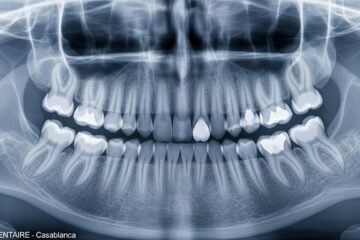

Radiographie Rétro-Alvéolaire : Tout Ce Que Vous Devez Savoir (Prix, Déroulement, Sécurité)

Votre dentiste vient de vous prescrire une radiographie rétro-alvéolaire et vous vous posez mille questions ? C’est une réaction tout à fait normale. Rassurez-vous immédiatement : cet examen est simple, rapide et totalement indolore. Au Maroc, il coûte environ 100 DH et ne dure que quelques secondes. Dans ce guide complet, vous découvrirez exactement ce […]

Radiographie de la Mandibule au Maroc : Prix, Déroulement et Tout Ce Qu’il Faut Savoir

Votre dentiste vient de vous prescrire une radiographie de la mandibule et vous vous posez mille questions ? Vous n’êtes pas seul. Chaque jour, des milliers de Marocains se demandent combien coûte cet examen, où le faire, et s’il est vraiment nécessaire. Bonne nouvelle : la radiographie de la mandibule est un examen courant, rapide […]